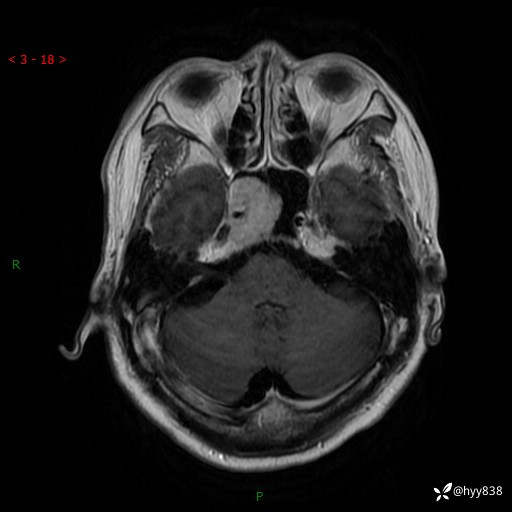

MRI增强(外院平扫)